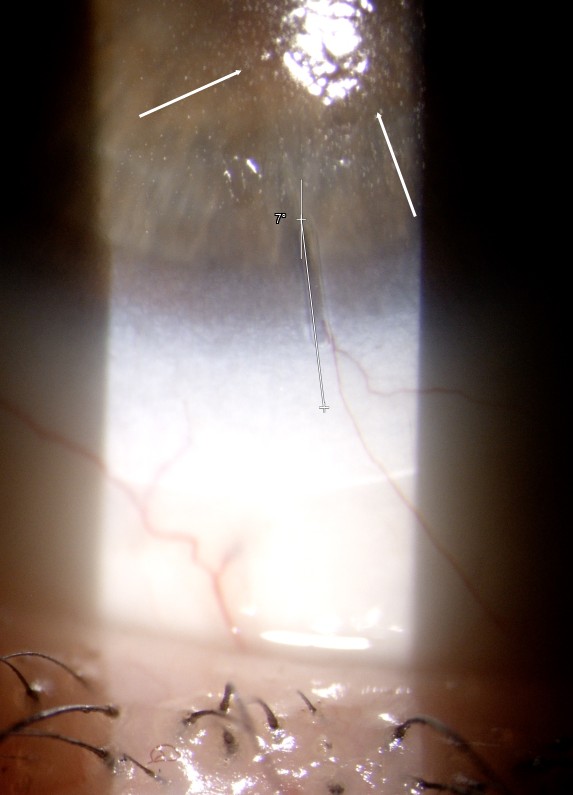

Controllo dopo 30 minuti: AV 10/10 OU, visione stabile e confortevole. Rotazione minima (≈7° OD), dinamica, centraggio e allineamento corretti. È stata evidenziata ridotta bagnabilità superficiale della LAC alla lampada a fessura (fig. 1, 2).